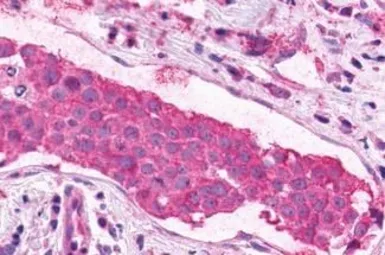

XPR1 antibody

Cat. No. GTX13290

ApplicationsICC/IF IHC-P